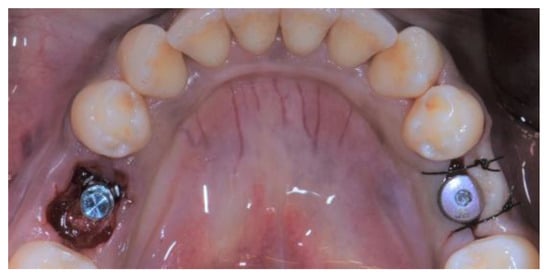

2.5. Individual Cases Description

- Case 1:

- Case 2:

- Case 3:

- Case 4:

- Case 5: